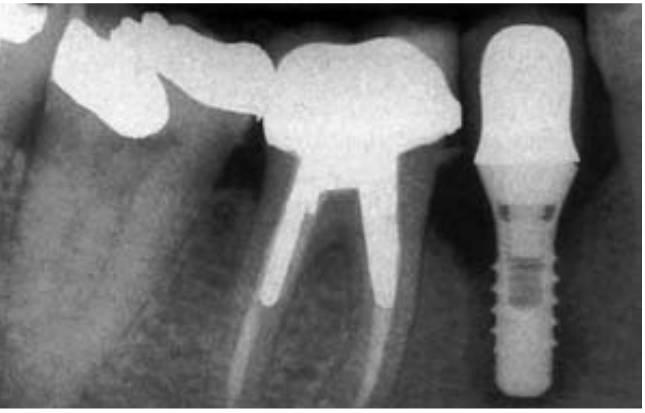

Las complicaciones más comunes relacionadas con los implantes son los problemas biomecánicos que se producen una vez cargado el implante. Un repaso a la literatura referente a los fracasos de implantes indica que estos problemas se producen primariamente durante los 18 meses posteriores a la carga inicial del implante. Estos fracasos iniciales de carga del implante se producen con más frecuencia en los de tipo de hueso más blando (fracaso del 16%) o en los implantes de menor longitud (fracaso del 17%). Estos dos grupos de fracasos están causados típicamente por factores biomecánicos. El hueso blando es demasiado débil para las fuerzas oclusales aplicadas en los implantes, o los implantes más cortos soportan demasiado estrés en la interfase hueso-implante (fig. 4-1).

Existen numerosas razones para que un implante fracase en su integración inicial con el hueso. Las causas primarias del fracaso están relacionadas con un excesivo calor durante la preparación de la osteotomía o un exceso de presión en la interfase implante-hueso en el momento de la inserción del implante21 (fig. 4-2). La presión excesiva en la inserción del implante se observa con más frecuencia con los diseños del cuerpo de tipo tornillo cónico. La fuerza de inserción del torque sobre un implante de diseño de cuerpo de tornillo cónico puede aplicar fuerzas excesivas sobre el hueso, lo que conlleva a una reabsorción y fracaso del implante.

Una causa adicional del fracaso quirúrgico son los micromovimientos del implan te mientras se establece la interfase en desarrollo (fig. 4-3). Un brazo fracturado es inmovilizado para evitar movimiento en el foco de fractura para disminuir el riesgo de una falta de unión fibrosa. Se ha observado que movimientos tan pequeños como de 20 micrones pueden causar la formación de una interfase fibrosa en el foco de fractura. Brunski observó el desarrollo de una interfase de tejido fibroso cuando un implante dental se mueve más de 100 micrones durante la cicatrización inicial. El protocolo original Bránemark empleaba un enfoque quirúrgico de dos etapas. Uno de los principales motivos de este concepto era el de colocar el implante en la región de hueso de la cresta o por debajo de ella para disminuir el riesgo de movimiento del implante durante la cicatrización ósea inicial. Schroeder sugirió también un período de cicatrización sin cargas para los implantes, aunque el implante fuera colocado en los tejidos gingivales o ligeramente superior a estos.

En algunas ocasiones, un implante puede fracasar poco tiempo después de haberse empezado a «integrar» en el hueso. Antes del fracaso, el implante parece tener una fijación rígida, y todos los indicadores clínicos están dentro de la normalidad. En cualquier caso, una vez que el implante está cargado, se vuelve móvil en el plazo de entre 6 y 18 meses (fig. 4-1). Esto ha sido denominado fracaso temprano por carga por Misch y Jividen. La causa de este fracaso temprano por carga suele ser un estrés excesivo para la interfase hueso-implante. Isidor permitió la integración de ocho implantes en mandíbulas de monos. Las coronas se sujetaban a los implantes cicatrizados con un exceso de contactos oclusales prematuros. Sobre un período de 20 meses, seis de los ocho implantes fracasaron (fig. 4-4). En estos mismos animales, ocho implantes integrados sin cargas oclusales llevaban unas anillas colocadas en el margen gingival para aumentar la retención de placa. Ninguno de estos implantes fracasó a lo largo de los siguientes 20 meses. Los autores concluyeron que en este modelo de animal, el estrés oclusal biomecánico era un mayor factor de riesgo para el fracaso temprano por carga que el componente biológico de la placa bacteriana.